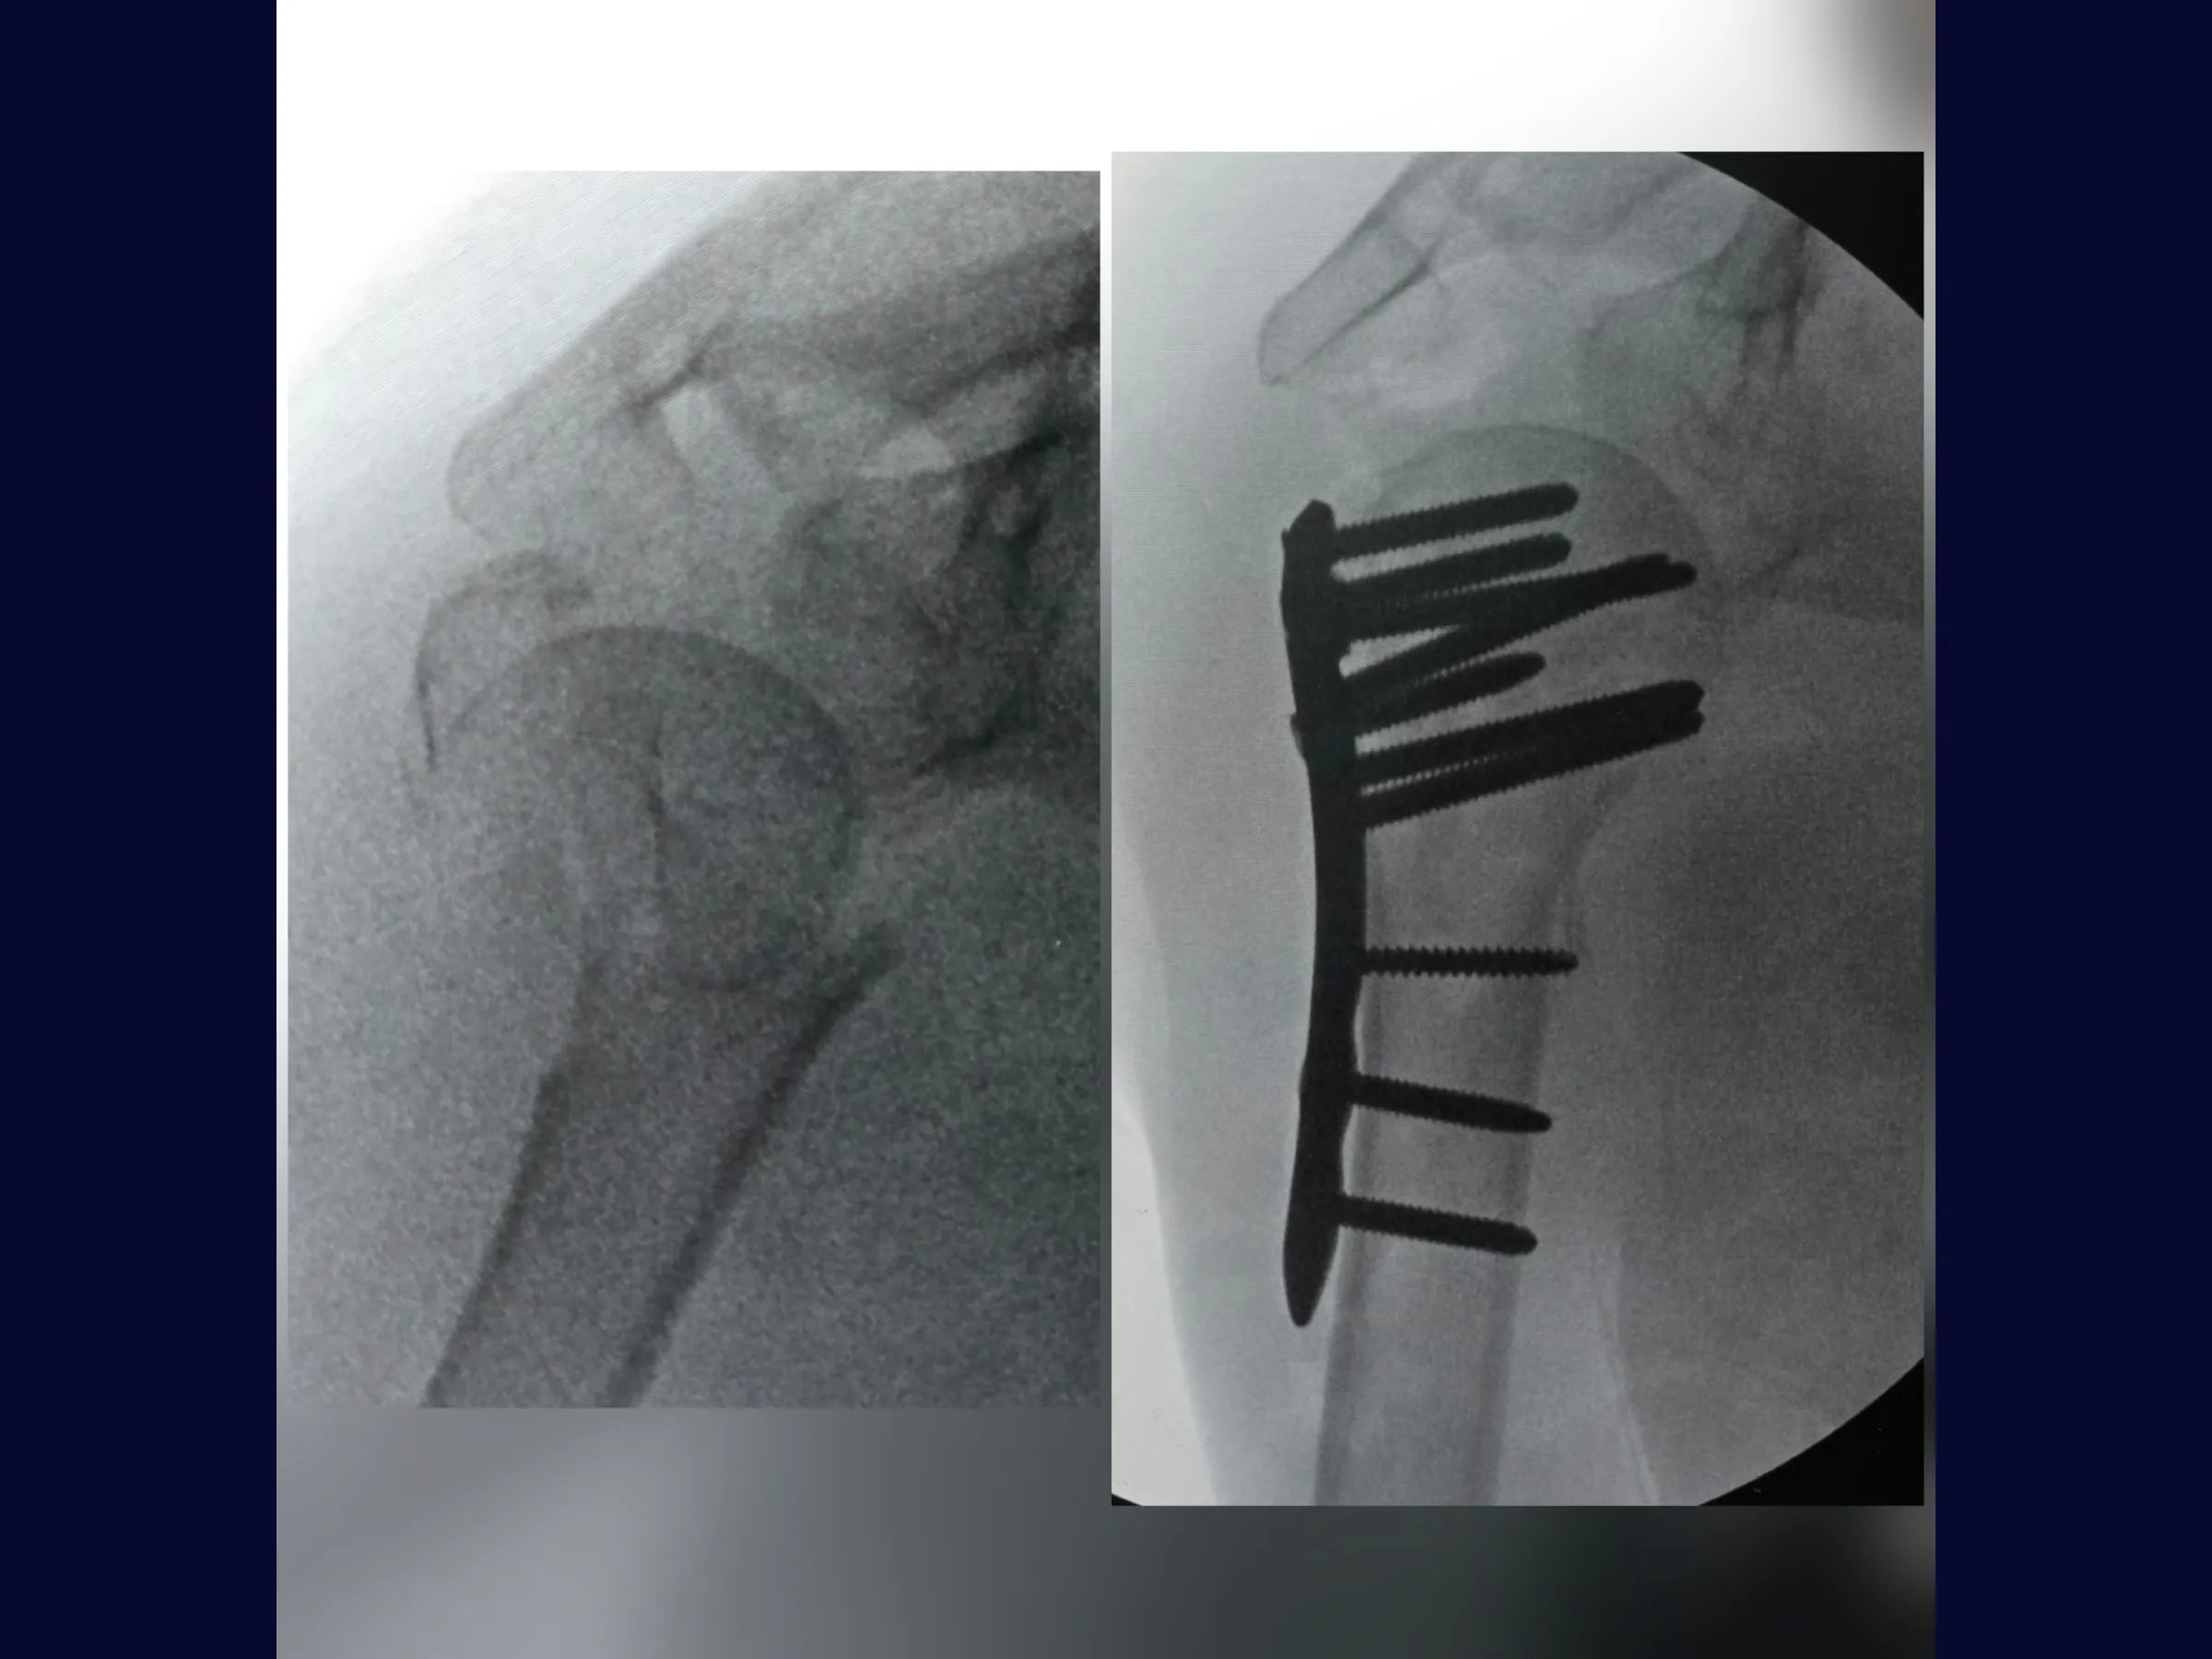

As fraturas complexas do úmero proximal, especialmente em quatro partes com impacto em valgo, exigem domínio técnico para restauração da anatomia e função.

Este treinamento apresenta, passo a passo, a reconstrução do úmero proximal por via deltopeitoral, com ênfase na redução anatômica das tuberosidades e fixação estável com placa bloqueada, demonstrada sob perspectiva cirúrgica detalhada.

- Fixação com placa bloqueada e parafusos do calcar;

- Liberação e Redução Precisa: Técnicas para reposicionar a cabeça impactada em valgo e realinhar tuberosidades.